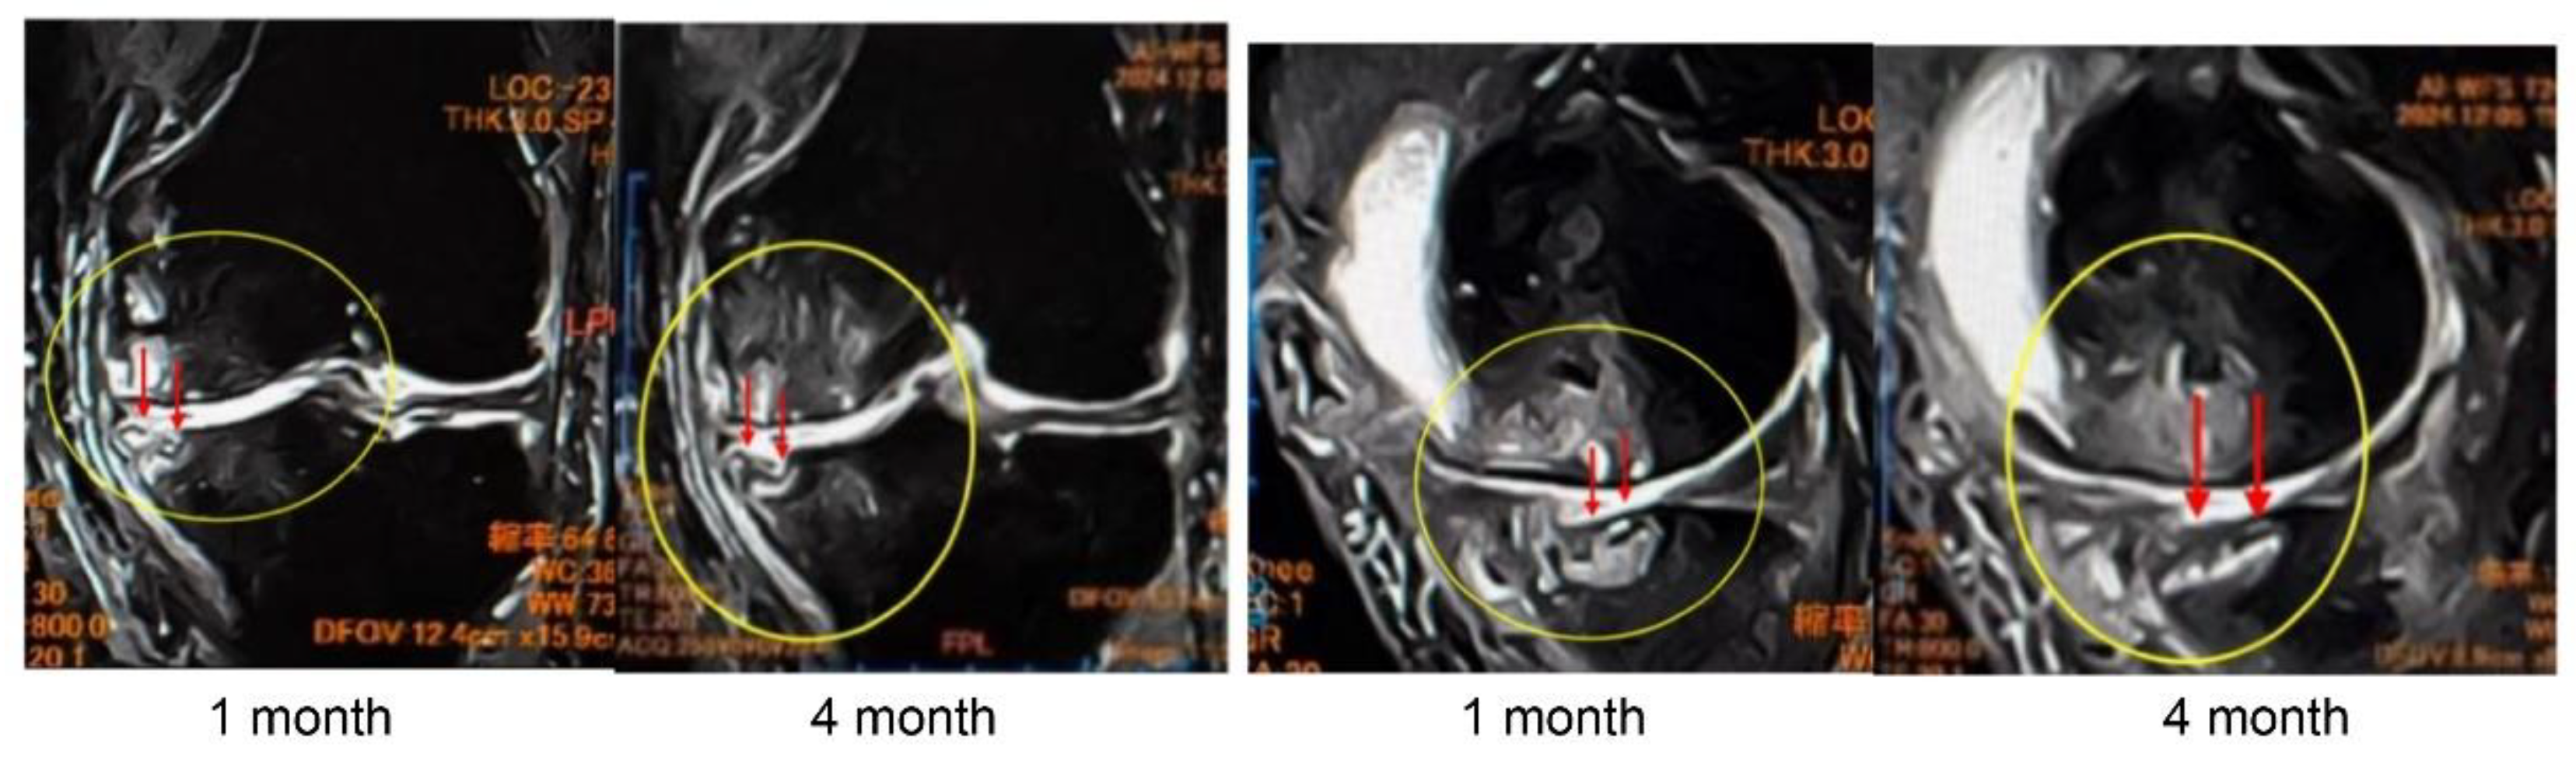

In Case 4 (

Figure 9), a 63-year-old male, sequential MRI changes following combined treatment with intra-articular and intraosseous MSC administration and ESWT were evaluated. At baseline, irregularities of the articular surface and a tear of the SBP were observed. At 1 month, early signs of repair became evident, and at 3 months, further progression of structural restoration was noted. At 6 months, near-complete reconstruction of the articular surface and SBP was achieved. These findings suggest that the synergistic effect of MSC administration combined with ESWT may contribute to the regeneration of cartilage and subchondral bone (

Figure 9a).

These images (

Figure 9b) represent magnified views of the joint surface from the T2-weighted images shown in

Figure 10a. Pretreatment findings revealed a BML and disruption of the articular surface. Progressive repair was observed at 1 month and 3 months after treatment. At 6 months, near-complete restoration of the articular surface and subchondral bone plate was evident.

Figure 10 (Case 5) shows T2-weighted MRI findings at 1 and 4 months after intraosseous MSC administration. In sagittal and coronal views, progressive subchondral bone collapse and depression of the articular surface were observed, which became more pronounced between 1 and 4 months. These morphological changes were accompanied by alterations in joint congruity, suggesting ongoing structural compromise that may predispose to secondary osteoarthritic changes.

Particularly in cases with extensive BML located adjacent to the articular surface, MSC administration may increase bone fragility, indicating the need for careful rehabilitation and load management.

Figure 9.

(a) MRI changes after combined intra-articular/intraosseous MSC administration and ESWT in a 63-year-old male. T1-weighted coronal views (top row) and T2-weighted coronal views (bottom row) at baseline, 1, 3, and 6 months. The targeted area (yellow circles) demonstrated near-complete restoration of the articular surface and SBP at 6 months. (b) Detailed observation of lesions in T2-weighted images. Enlarged views of the joint surface from the T2-weighted images shown in

Figure 10.

Progression of subchondral bone collapse after intraosseous MSC administration (T2-weighted images). MRI scans at 1 month and 4 months post-treatment. The left images show sagittal views, and the right images show coronal views. Yellow circles and red arrows indicate progressive subchondral bone collapse and depression of the articular surface from 1–4 months. In cases with extensive BML near the articular surface, MSC administration may increase bone fragility, necessitating cautious rehabilitation and load management.